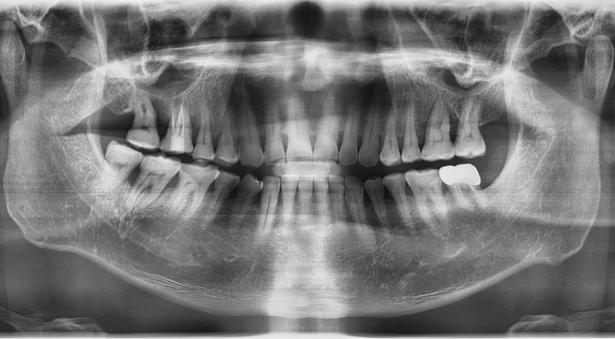

Pre-operative Radiograph